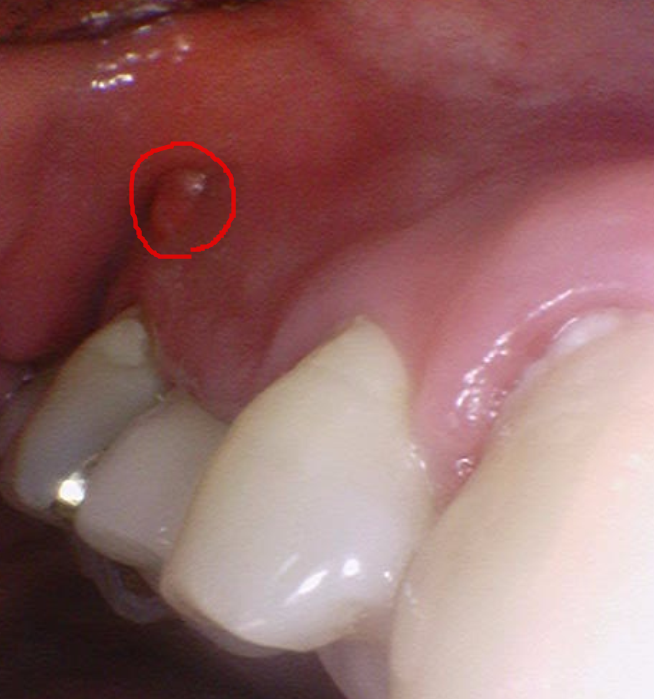

농양이 빠져나올 길이 없어

잇몸 밖으로 볼록~

여드름 난 것처럼 부풀었습니다.